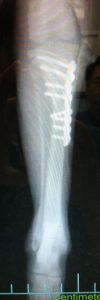

橈骨骨折(不適切な外固定により長時間放置された例)